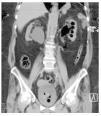

En la Figura 3 se observa como la vena ovárica izquierda ingresa a la vena renal ipsilateral, produciendo ectasia ureteral desde el cruce de las ilíacas, se demuestra que es el sitio donde se cruza el uréter y la vena ovárica, allí se manifiesta la escotadura antes mencionadas, también demostrándose en esta figura la ectasia derecha con gas parenquimatoso hacia el polo superior. En la Figura 4 resalta del lado derecho, justo donde se cruza la vena ovárica con el uréter es donde se produce la ectasia a nivel de la bifurcación de la aorta en ilíacas primitivas, y del lado izquierdo en el cruce ureteral con los vasos ilíacos nuevamente se cruza con la vena ovárica produciendo ectasia.

Figura 4. Lado derecho: cruce de la vena ovárica con uréter, es donde se produce la ectasia a nivel de la bifurcación de la aorta en ilíacas primitivas. Lado izquierdo: en el cruce ureteral con los vasos ilíacos, nuevamente se cruza con la vena ovárica produciendo ectasia retrógrada.